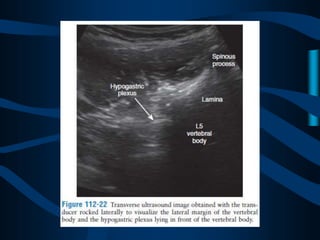

ABORDAJE ANTERIOR

CON UNA AGUJA

EFECTOS SECUNDARIOS YCOMPLICACIONES LA PROXIMIDAD DE LOS NERVIOS HIPOGASTRICOS A LOS VASOS ILIACOS CONFIERE UN RIESGO DE SANGRADO O INYECCION INTRAVASCULAR INADVERTIDA. INFECCIONES LOCALES E INTRA ABDOMINALES, ASI COMO LA SEPSIS CON CONTRAINDICACIONES ABSOLUTAS PARA ESTE ABORDAJE. EXISTE EL RIESGO DE PRODUCIRSE PERITONITIS Y ABSCESOS INTRABDOMINALES DEBIDO AL PASO DE LA AGUJA POR LAS VISCERAS ABDOMINALES.